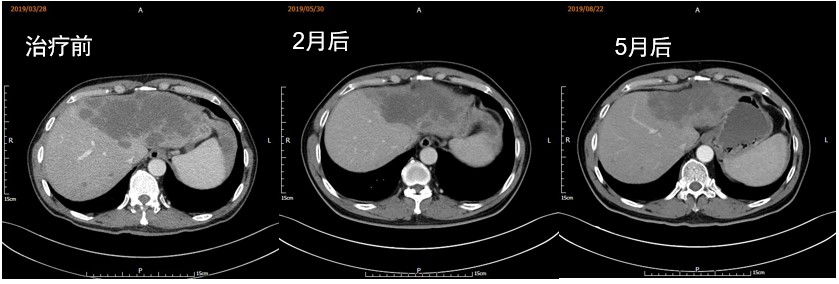

推荐免疫治疗,患者经过比较,选择信迪利单抗,2019年3月29日至今共行9周期信迪利单抗联合仑伐替尼治疗:信迪利单抗200mg/次,仑伐替尼12 mg/d,每3周为1个疗程。信迪利单抗用药时间分别为2019年3月29日、4月19日、5月10日、5月31日、6月21日、7月12日、8月2日、8月23日、9月13日。治疗2个月后复查,肝脏肿瘤较前明显缩小,综合评价PR;5个月后复查病灶相较前次继续缩小。治疗期间出现皮疹,但症状轻微。

患者中老年男性,诊断为肝内胆管细胞癌伴腹腔淋巴结转移。基因检测结果示:TMB 11.06mut/MB;MMR:pMMR;MSI:MSS。患者无手术指征,一线方案采用信迪利单抗联合仑伐替尼治疗,期间出现皮疹,但症状轻微。患者用药后效果显著,2个月后复查肿瘤明显缩小,5个月后复查显示肿瘤较前继续缩小,综合评价PR。现仍行原方案治疗。